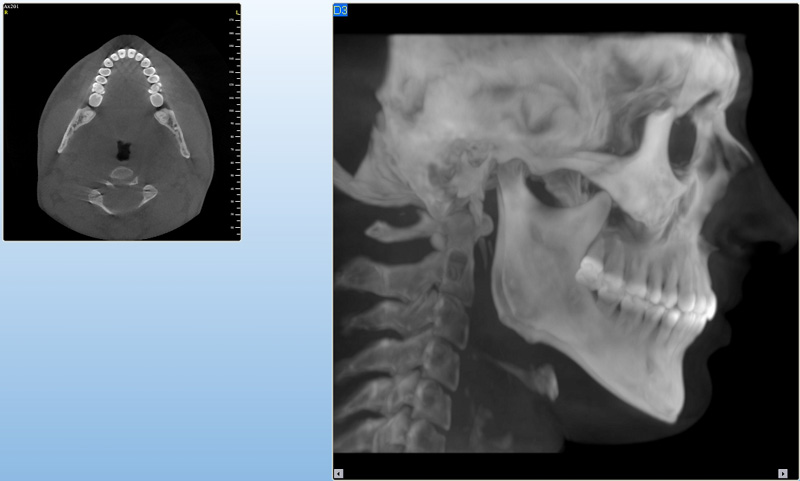

3D DVT - NewTom

Je speciální zubní digitální tříprostorový tomograf (3D), který umožňuje na základě jediného

snímkování vytvořit všechny typy RTG zobrazení, které jsou pro lékaře potřebné. Díky používané technologii tzv. „kuželového paprsku“ a speciálním senzorům je

výrazně zmenšená dávka záření - o více jak 80% proti klasickému CT vyšetření. To je významné zejména u dětí. Pomocí tohoto přístroje je možné zjisti skutečnou situaci v čelistních kostech pacienta tedy množství kosti - můžeme změřit skutečnou šířku i výšku kosti, i kvalitu kosti (hustotu) v místě uvažované implantace. 3D (tříprostorové) zobrazení umožňuje zvýšit prostorovou představu operatéra ještě před vlastní operací a zároveň pacientovi lépe objasnit a ukázat oblast plánovaného zavedení implantátu.

Pacient „neumí číst“ RTG snímky, ale díky 3D zobrazení vidí „svoji skutečnou čelist“

- např. jak je nízká či úzká, vidí průběh nervu nebo velikost čelistní dutiny, což mu umožní i pochopení nutnosti v některých případech provést pomocné zákroky ještě před vlastním zavedením implantátu (viz. kostní štěp, sinus lift, kostní granulát...).

Vyšetření pomocí tohoto přístroje používáme i ve stomatochirurgii (zlomeniny čelistí, zuby moudrosti, cysty, onemocnění čelistního kloubu), ortodoncii (retinované zuby, nadpočetné zuby), parodontologii atd.

NewTom Giano

Jedná se o nejnovějším přístroj ze skupiny dentálních hybridních CBCT (3D) + 2D (pan i ceph) systémů. Opět umožňuje na základě jediného snímkování vytvořit všechny typy RTG zobrazení, které jsou pro lékaře potřebné. Používaná technologii tzv. „kuželového paprsku“ a speciální senzory pro minimální zátěž při snímkování pacienta.

Vyšetření pomocí tohoto přístroje (nebo

3D DVT - NewTom) a získaná data používáme

pro každou implantaci, dále ve stomatochirurgii (zlomeniny čelistí, zuby moudrosti, cysty, onemocnění čelistního kloubu), ortodoncii (retinované zuby, nadpočetné zuby), parodontologii atd.